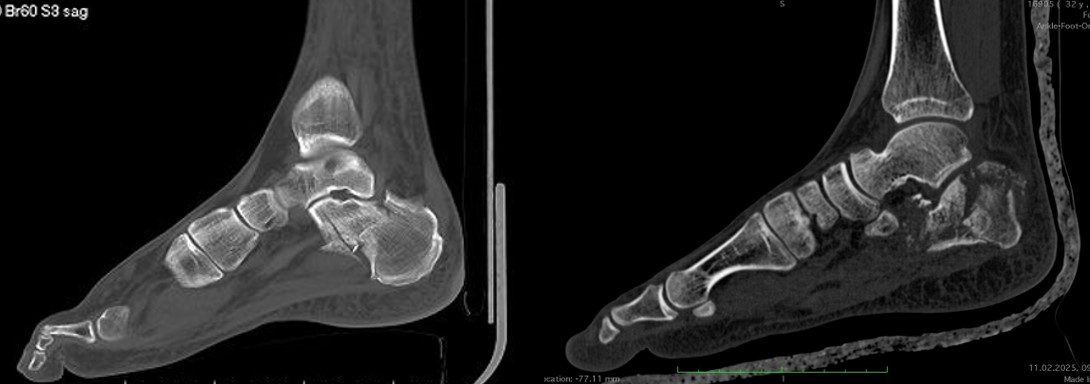

Але рентген — лише силует, тінь реальності. Справжню карту руйнувань малює комп’ютерна томографія (КТ) — безжальний картограф, що шар за шаром зрізає тканини, показуючи перелом у всій його тривимірній жорстокості. Тут видно кожен уламок, кожну тріщину, кожне зміщення. КТ дозволяє побачити те, що приховане від звичайного погляду — як суглобова поверхня розламана на шматки, наче дзеркало, що впало на підлогу.

Саме ці знімки визначають, чи зможе лікар зібрати цю «складанку» назад, чи доведеться жити з компромісом.

Тип перелому визначає долю. Простий позасуглобовий перелом горбистості пʼяткової кістки без зміщення — це місяць у гіпсі, три місяці обережності, і далі майже нормальне життя. Але складний внутрішньосуглобовий перелом з пошкодженням суглобової поверхні на десять уламків — це рік реабілітації, операція з сумнівним результатом, артроз через пʼять років, артродез через десять. Це дві різні історії під однією назвою "перелом пʼяткової кістки".